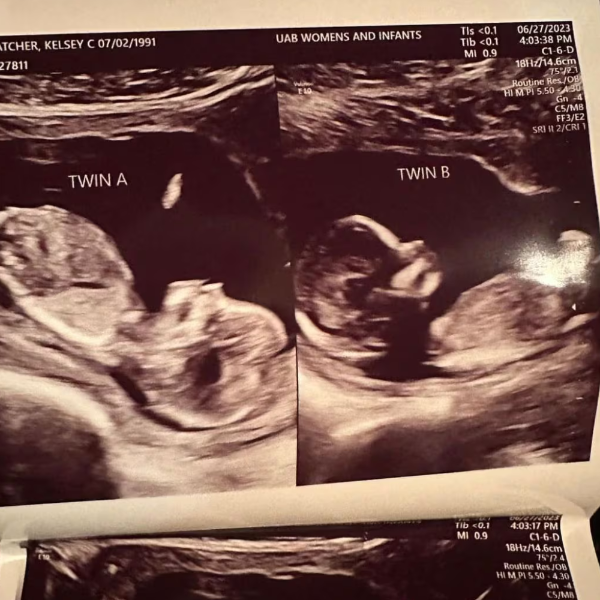

Durante un ultrasonido de rutina en mayo, la masajista terapéutica y madre de tres hijos, se enteró no solo de que esta vez tendría mellizos, sino que cada feto estaba presente en cada uno de sus úteros.

"Lo que probablemente sucedió es que ovuló de manera separada y un óvulo bajó por cada trompa de Falopio, es decir, bajó a cada lado del útero, y luego los espermatozoides viajaron hacia cada útero por separado y la fertilización se produjo separadamente", dijo al programa "Good Morning América" de ABC Shweta Patel, la ginecobstetra que atiende a Hatcher en el Centro de Mujeres e Infantes de la Universidad de Alabama, en Birmingham.